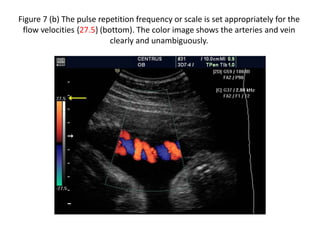

Figure 7 (b) The pulse repetition frequency or scale is set appropriately for the

flow velocities {27.5} (bottom). The color image shows the arteries and vein

clearly and unambiguously.

Figure 7 (a):Color flow imaging: effects of pulse repetition frequency or scale. (above) The pulse repetition frequency or scale is set low {11.0} (yellow arrow). The color image shows ambiguity within the umbilical artery and vein and there is extraneous noise.

Figure 7 (b)The pulse repetition frequency or scale is set appropriately for the flow velocities {27.5} (bottom). The color image shows the arteries and vein clearly and unambiguously.